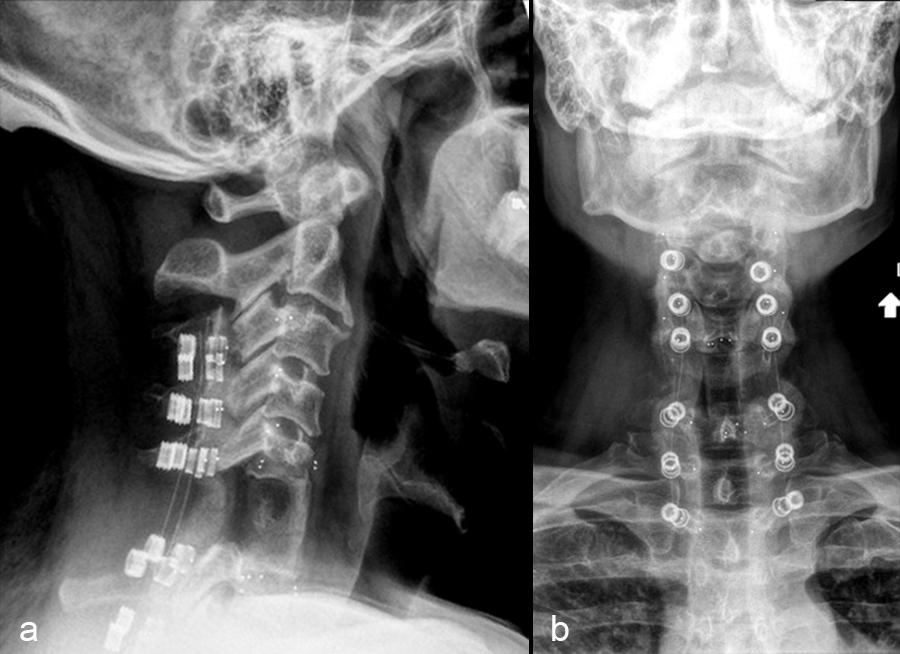

A 47-year-old male presented with neck pain. Upon examination, he was neurologically intact. He underwent an MRI of the cervical spine that demonstrated a non-enhancing T1-hypointense and T2-hyperintense lesion (Fig 1).

The patient underwent a CT guided biopsy that demonstrated a brachyury positive lesion consistent with a chordoma versus benign notochordal tumor. He underwent a two-stage operation for en bloc resection of the lesion. Cervical spine stabilization was achieved using CMORE® Carbon/PEEK implants. The radiolucent nature of these implants permits artifact-free postoperative imaging and more precise radiation treatment, an important consideration in patients with spinal tumors.

The first stage was a posterior approach with a C3-T3 instrumented fusion using CMORE® Carbon/PEEK lateral mass and pedicle screws (Fig 2) with resection of the posterior elements of C6, mobilization of the C6 and C7 nerve roots and vertebral arteries bilaterally. The second stage was a left sided anterior cervical approach with completion of the C6 spondylectomy and en bloc resection of the C6 lesion. The resected lesion tissue is shown in Fig 3.